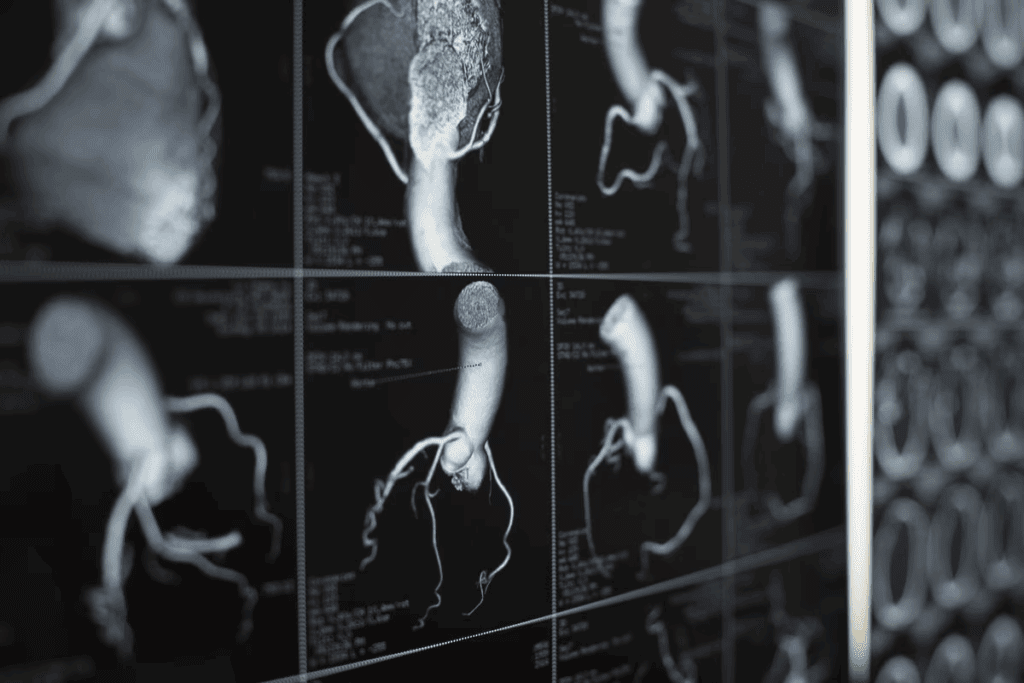

Acute coronary syndrome (ACS) is a serious condition where the heart’s blood flow is suddenly blocked. At Liv Hospital, we are committed to providing expert care and guidance to help you understand the risks and symptoms associated with ACS. Discover acute coronary artery disease risk factors and essential symptoms for early detection.

It’s important to know about Acute Coronary Syndrome (ACS). It’s a group of heart problems, including heart attacks and unstable angina. ACS is a serious condition that needs quick treatment to protect the heart.

ACS happens when blood flow to the heart suddenly drops. This can cause heart attacks and unstable angina. The main reason is when a plaque in a heart artery bursts, causing a blood clot.

Coronary artery disease (CAD) is the main cause of ACS. CAD makes heart arteries narrow or block. This happens when plaque, made of fat and cholesterol, builds up and ruptures.